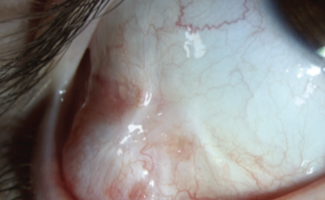

The authors report on the first known case of pediatric conjunctival hidrocystoma, highlighting the effectiveness of an integrative approach to diagnosis and treatment.